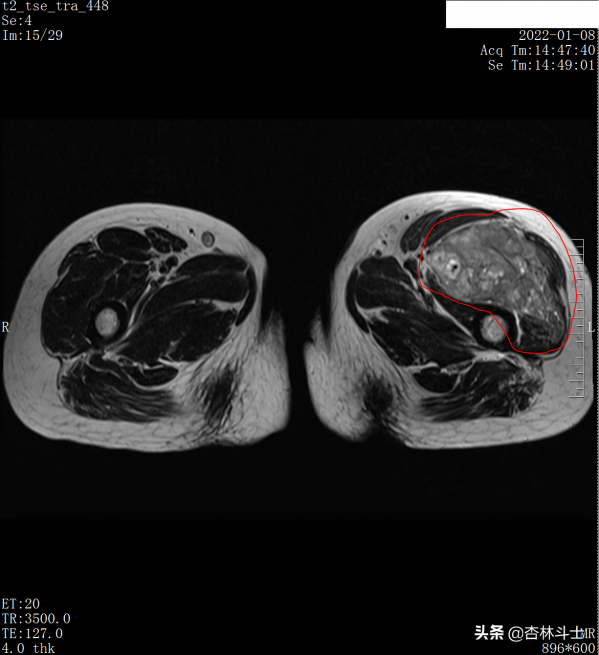

入院後查了左大腿3T磁共振平掃+增強,如圖示:

t2 橫斷位,左股骨上段前方不規則軟組織腫塊,與正常肌肉相比呈混雜稍高訊號